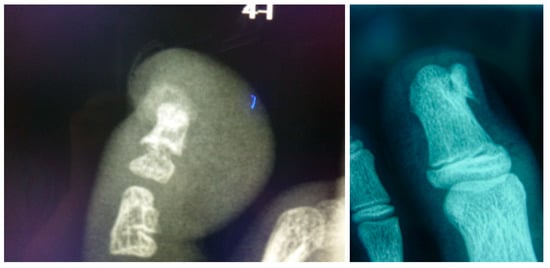

Surgical Treatment on Subungual Osteochondromas in Paediatric Feet: A Case Series Study

3.2. Clinical Features before Intervention